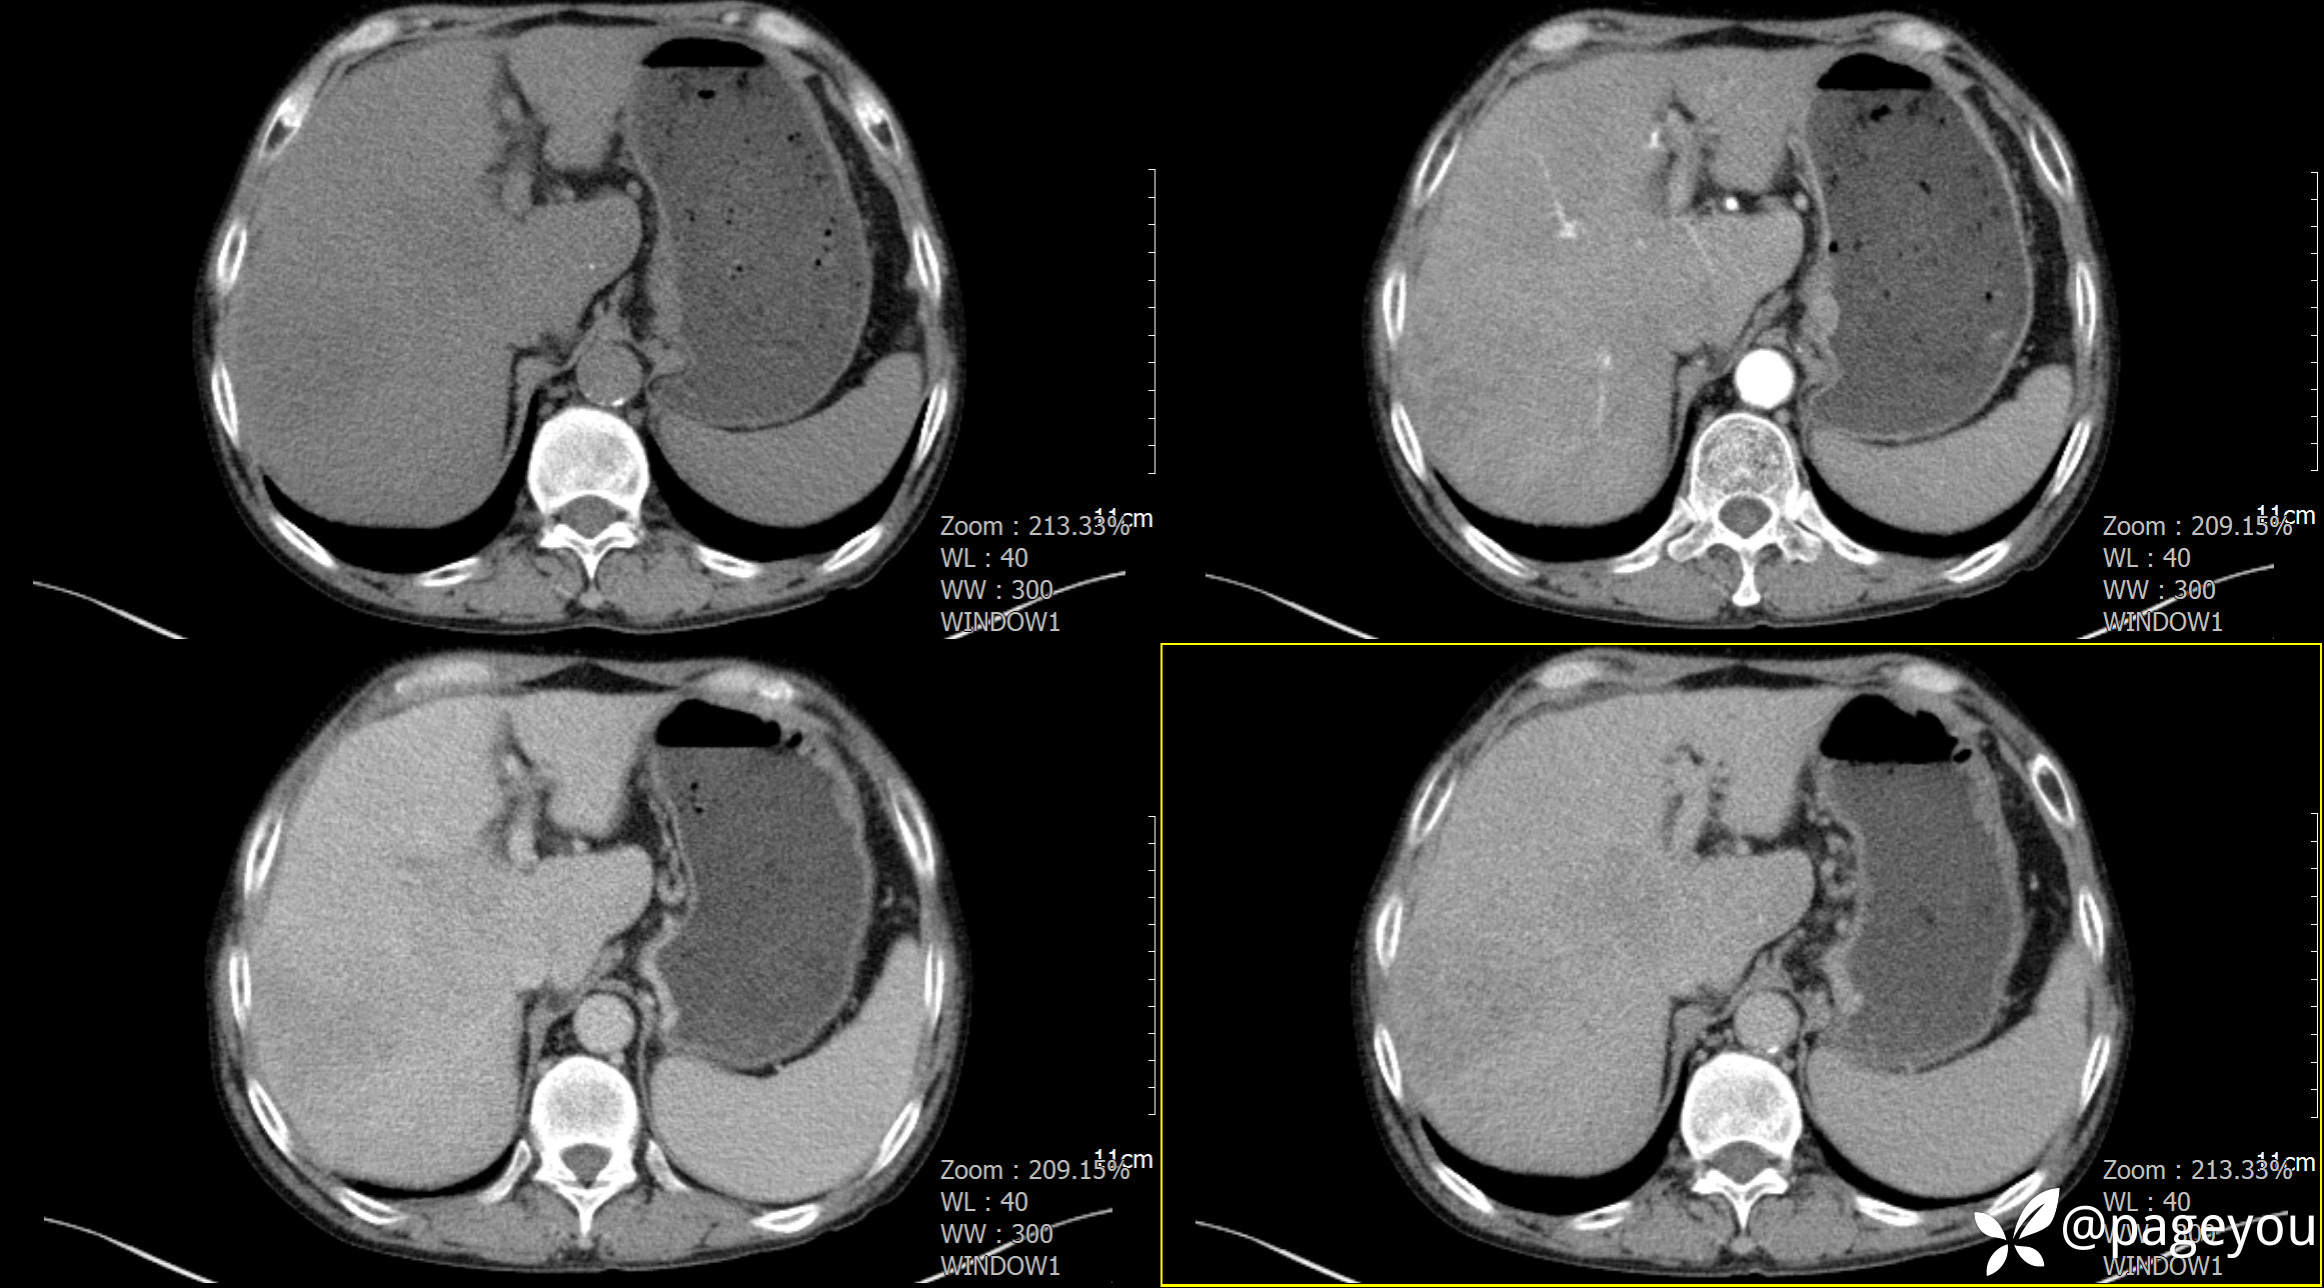

CT检查: